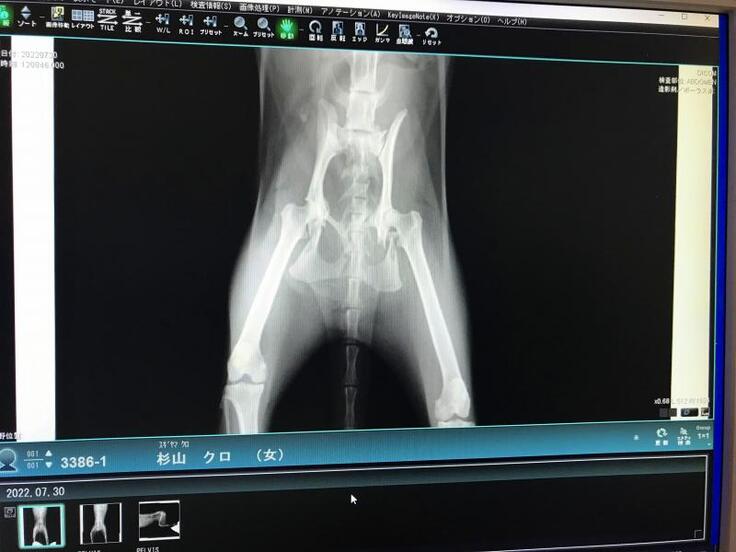

脚が立たないようなので仔猫2匹とクロちゃんを一緒に保護して動物病院で診察してもらうと、骨盤骨折していました。

初診のレントゲンでは骨盤の左側が骨折という診断で手術を受けましたが、手術後のレントゲンで右側も骨折していて、粉砕骨折しているという結果でした。

2回目の手術を受けて今はリハビリ中です。

交通事故に遭ったのだと思いますが、骨盤骨折して立てない動かない脚を前脚だけで引き摺って仔猫の元に帰ろうともがいて頑張って家の前まで帰って来ていたクロちゃん、なんとかうまく骨がつながって普通に歩いて走ってジャンプできるようになって欲しいと思います。

骨盤骨折しても必死で仔猫の元に帰えろうとしていたクロちゃんの骨盤骨折(粉砕骨折)を手術して元のように歩いて走ってできるようにしてやりたい。

長く待てないので、既に骨盤骨折の手術を2回受けました。

今は徐々に回復してヨタヨタしながらでも歩けるようになっていてリハビリ中です。